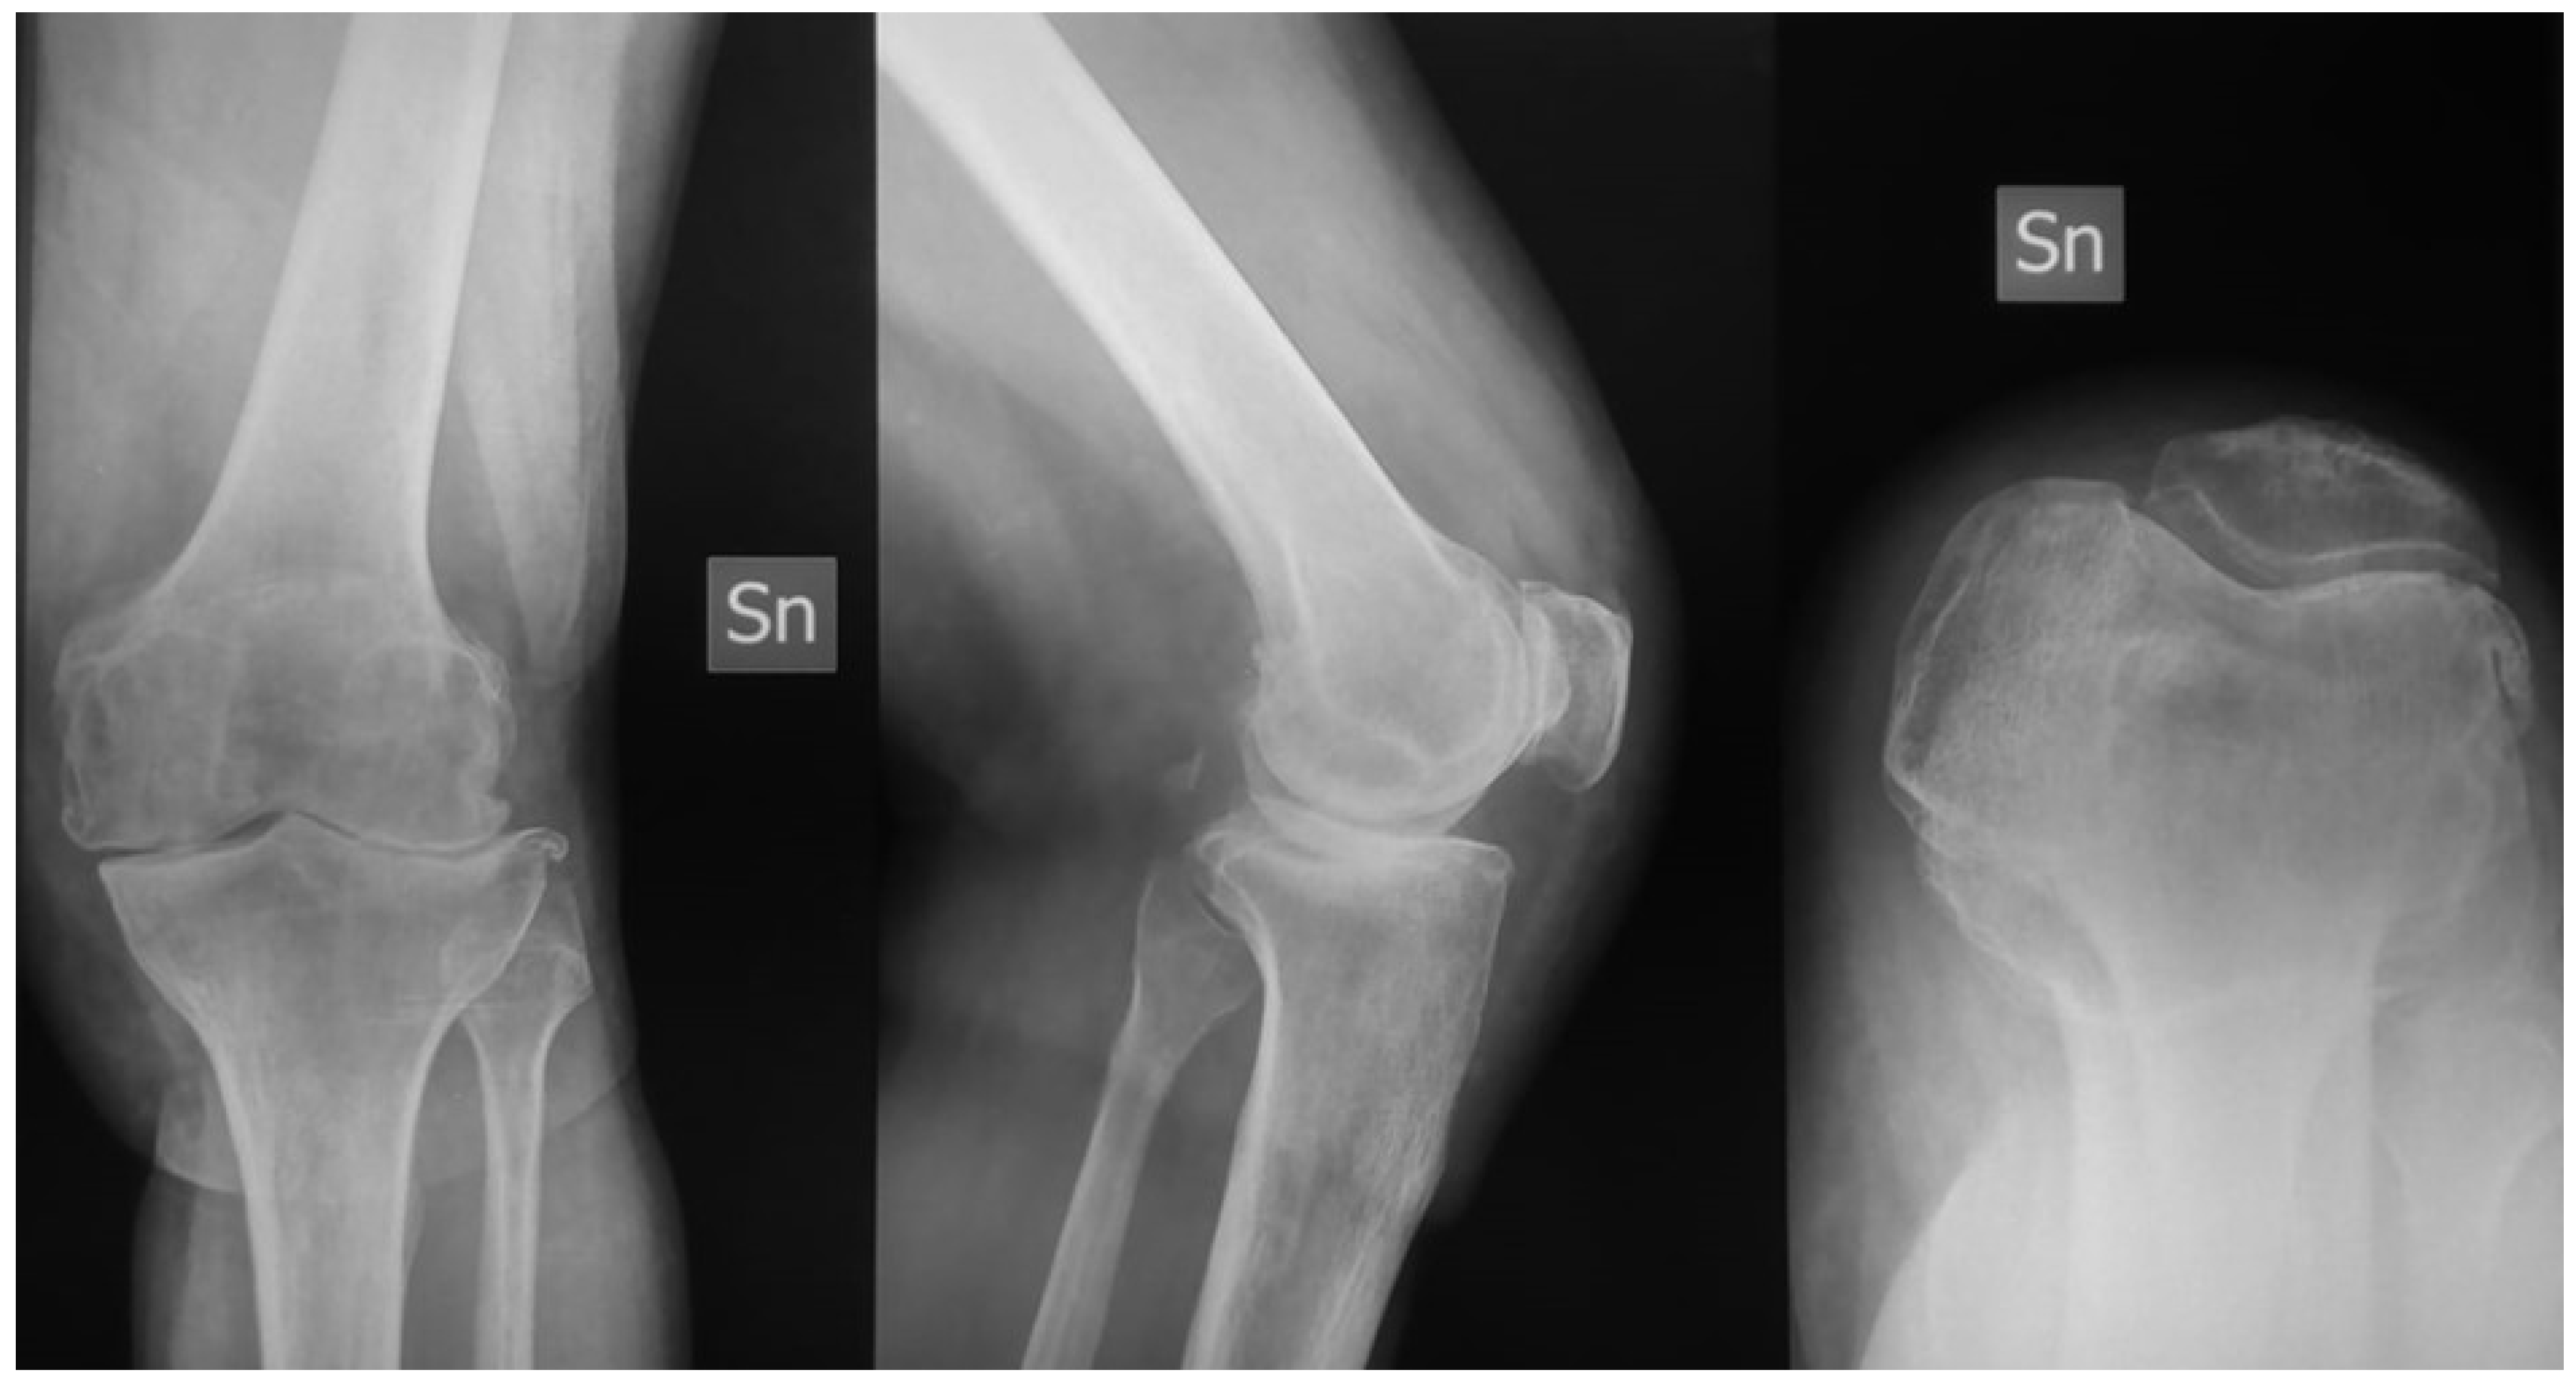

| Kellgren Lawrence classification | |||

| Grade 3 | 11 (37–93%) | // | // |

| Grade 4 | 18 (62.07%) | // | // |